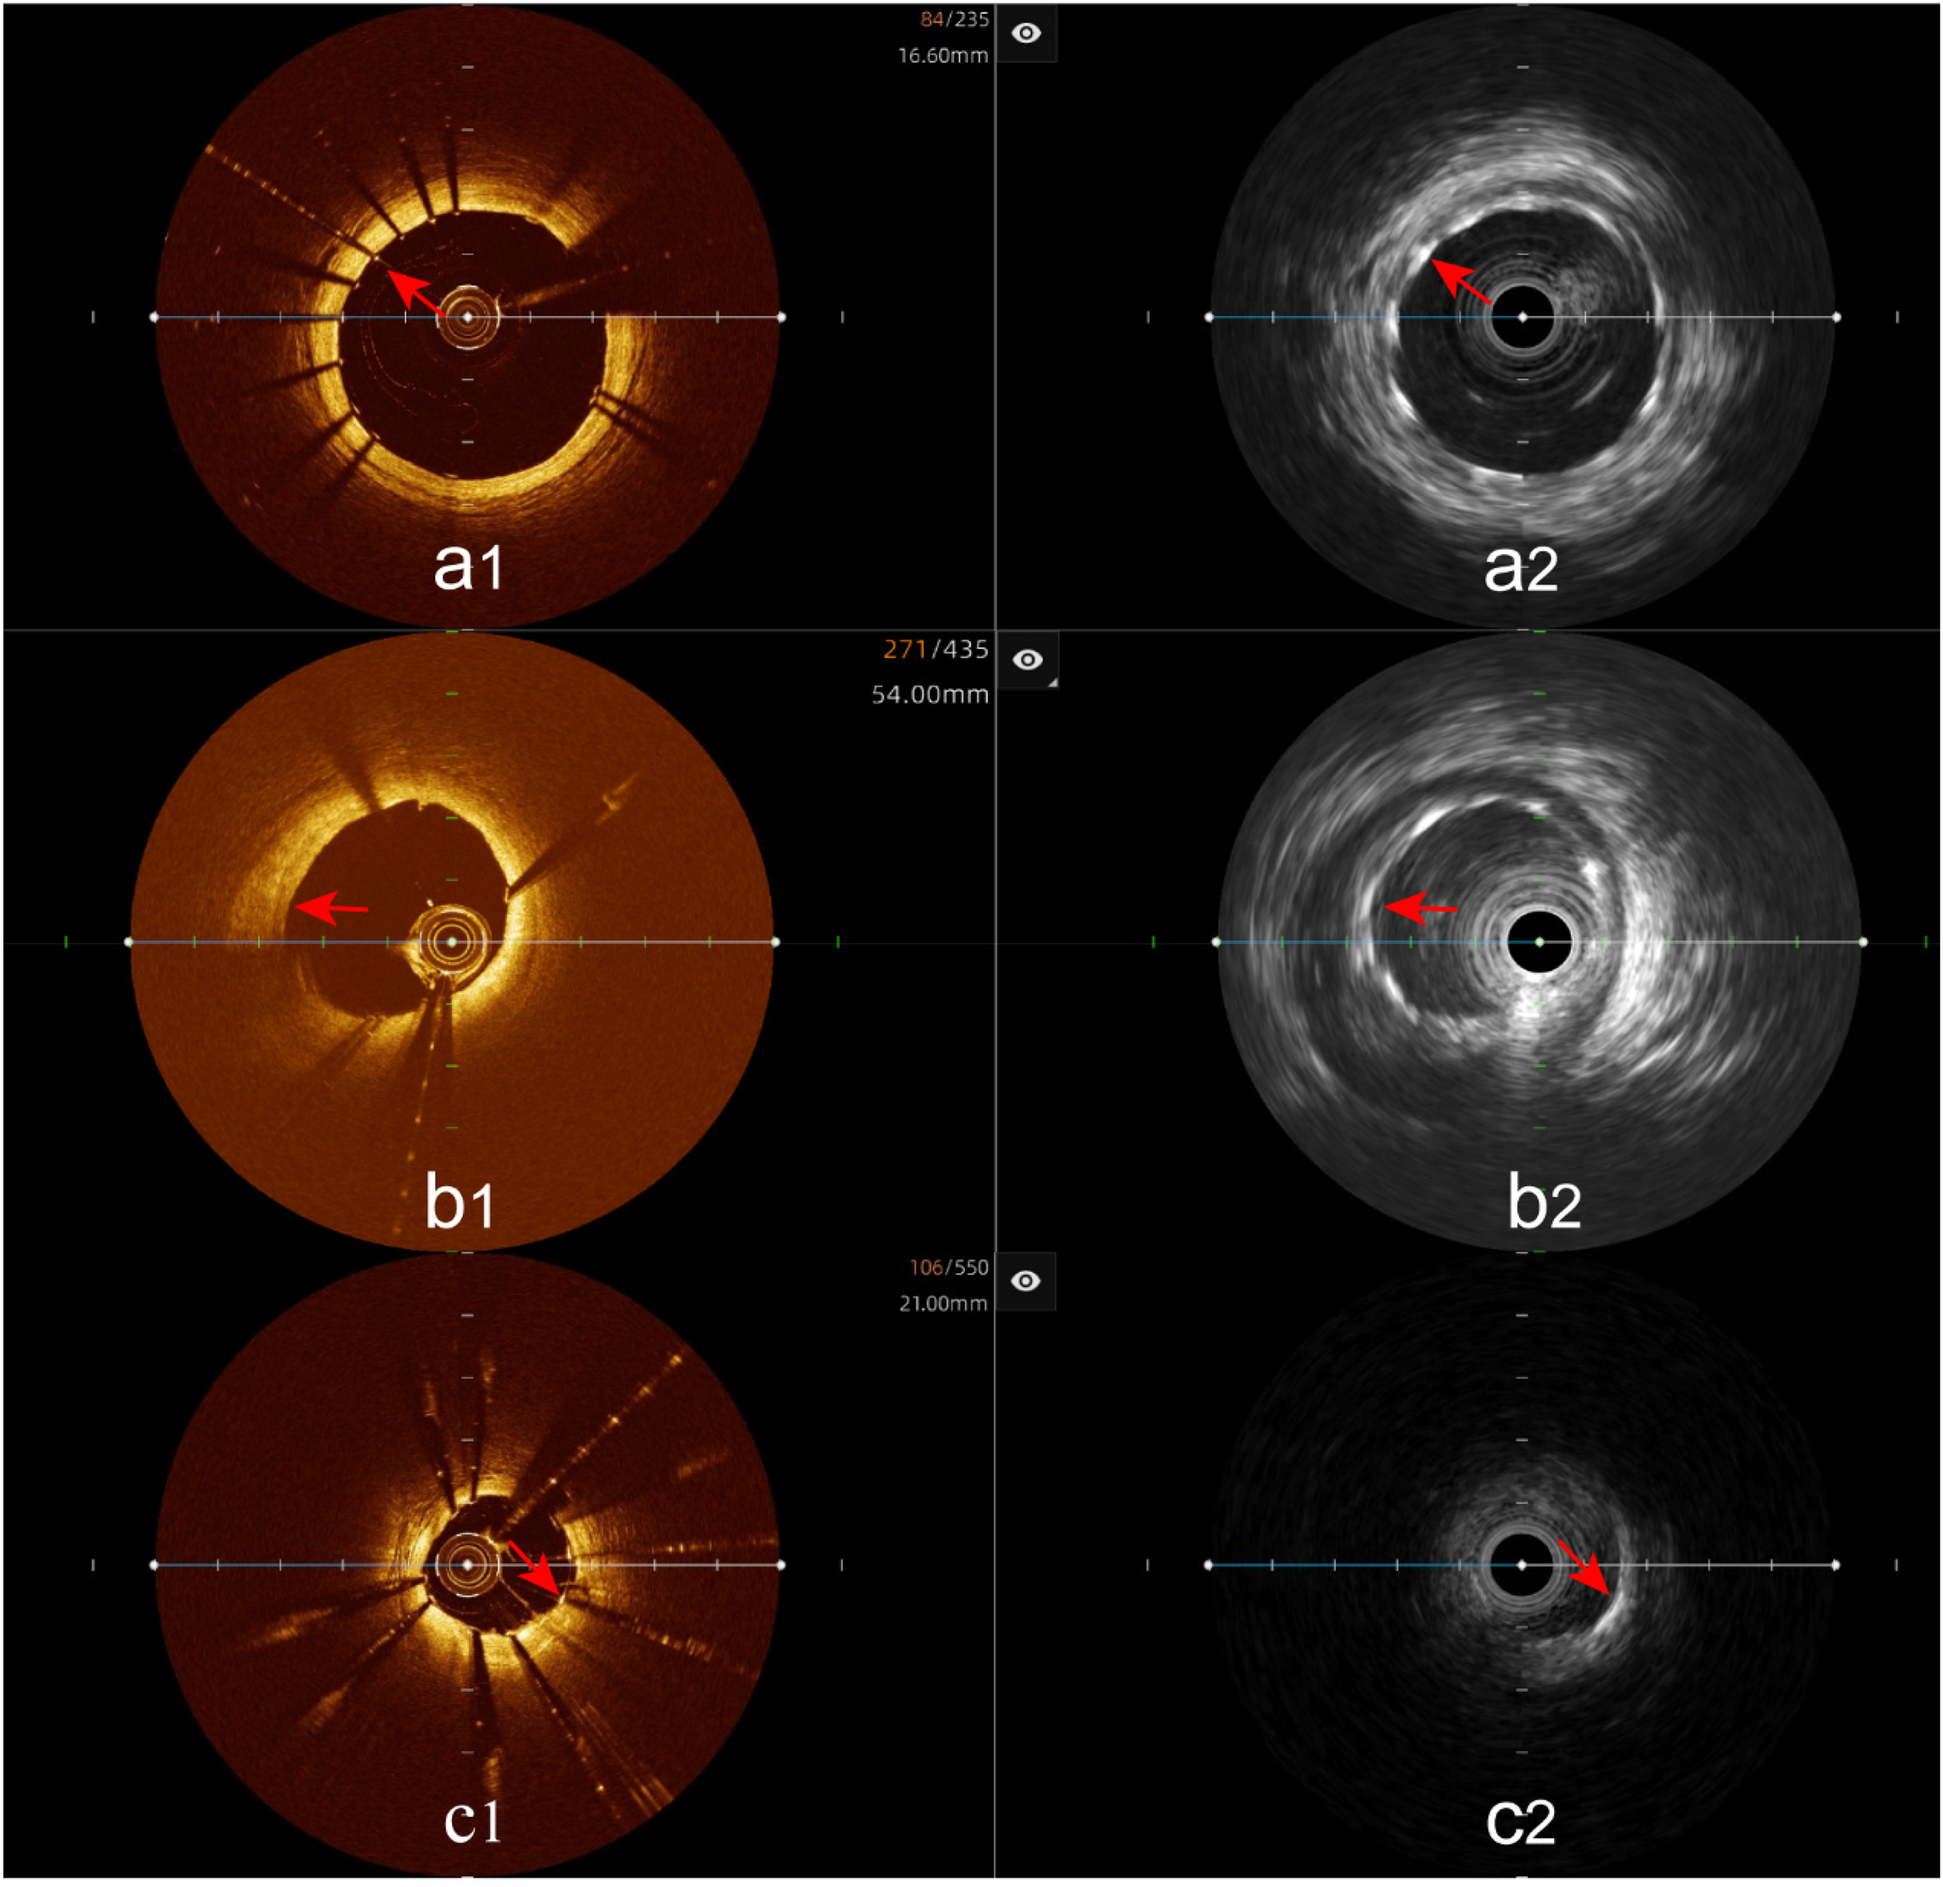

Figure 7

Immediate evaluation of the hybrid IVUS-OCT images after coronary stenting (full clarity of stent capture rate). (a1,a2) OCT and IVUS clearly show the stent. (b1) OCT shows unclear stent visualization, (b2) IVUS clearly shows the stent; (c1) OCT clearly shows the stent, (c2) IVUS shows unclear stent visualization.

Incomplete stent apposition: The hybrid IVUS-OCT imaging system identified 23 cases of incomplete stent apposition, compared with OCT detecting 23 (100%) and IVUS detecting 8 (34.78%) (P < 0.001;Figure 9;Table 3;Figure 8).

Figure 9

Immediate evaluation of the hybrid IVUS-OCT images after coronary stenting (incomplete stent apposition). (d1,d2) OCT and IVUS clearly show incomplete stent apposition.

Tissue protrusion: The hybrid IVUS-OCT imaging system identified 10 cases of tissue protrusion, compared with OCT detecting 10 (100%) and IVUS detecting 2 (20%) (P = 0.001;Figure 10;Table 3;Figure 8).

Figure 10

Immediate evaluation of the hybrid IVUS-OCT images after coronary stenting (tissue protrusion). (e1) OCT shows tissue protrusion; (e2) IVUS cannot visualize tissue protrusion.

Stent edge dissection: The hybrid IVUS-OCT imaging system identified 10 cases of stent edge dissection, compared with OCT detecting 10 (100%) and IVUS detecting 7 (70%) (P = 0.211;Figure 11;Table 3;Figure 8).

Figure 11

Immediate evaluation of the hybrid IVUS-OCT images after coronary stenting (stent edge dissection). (f1,f2) OCT and IVUS clearly show stent edge dissection.